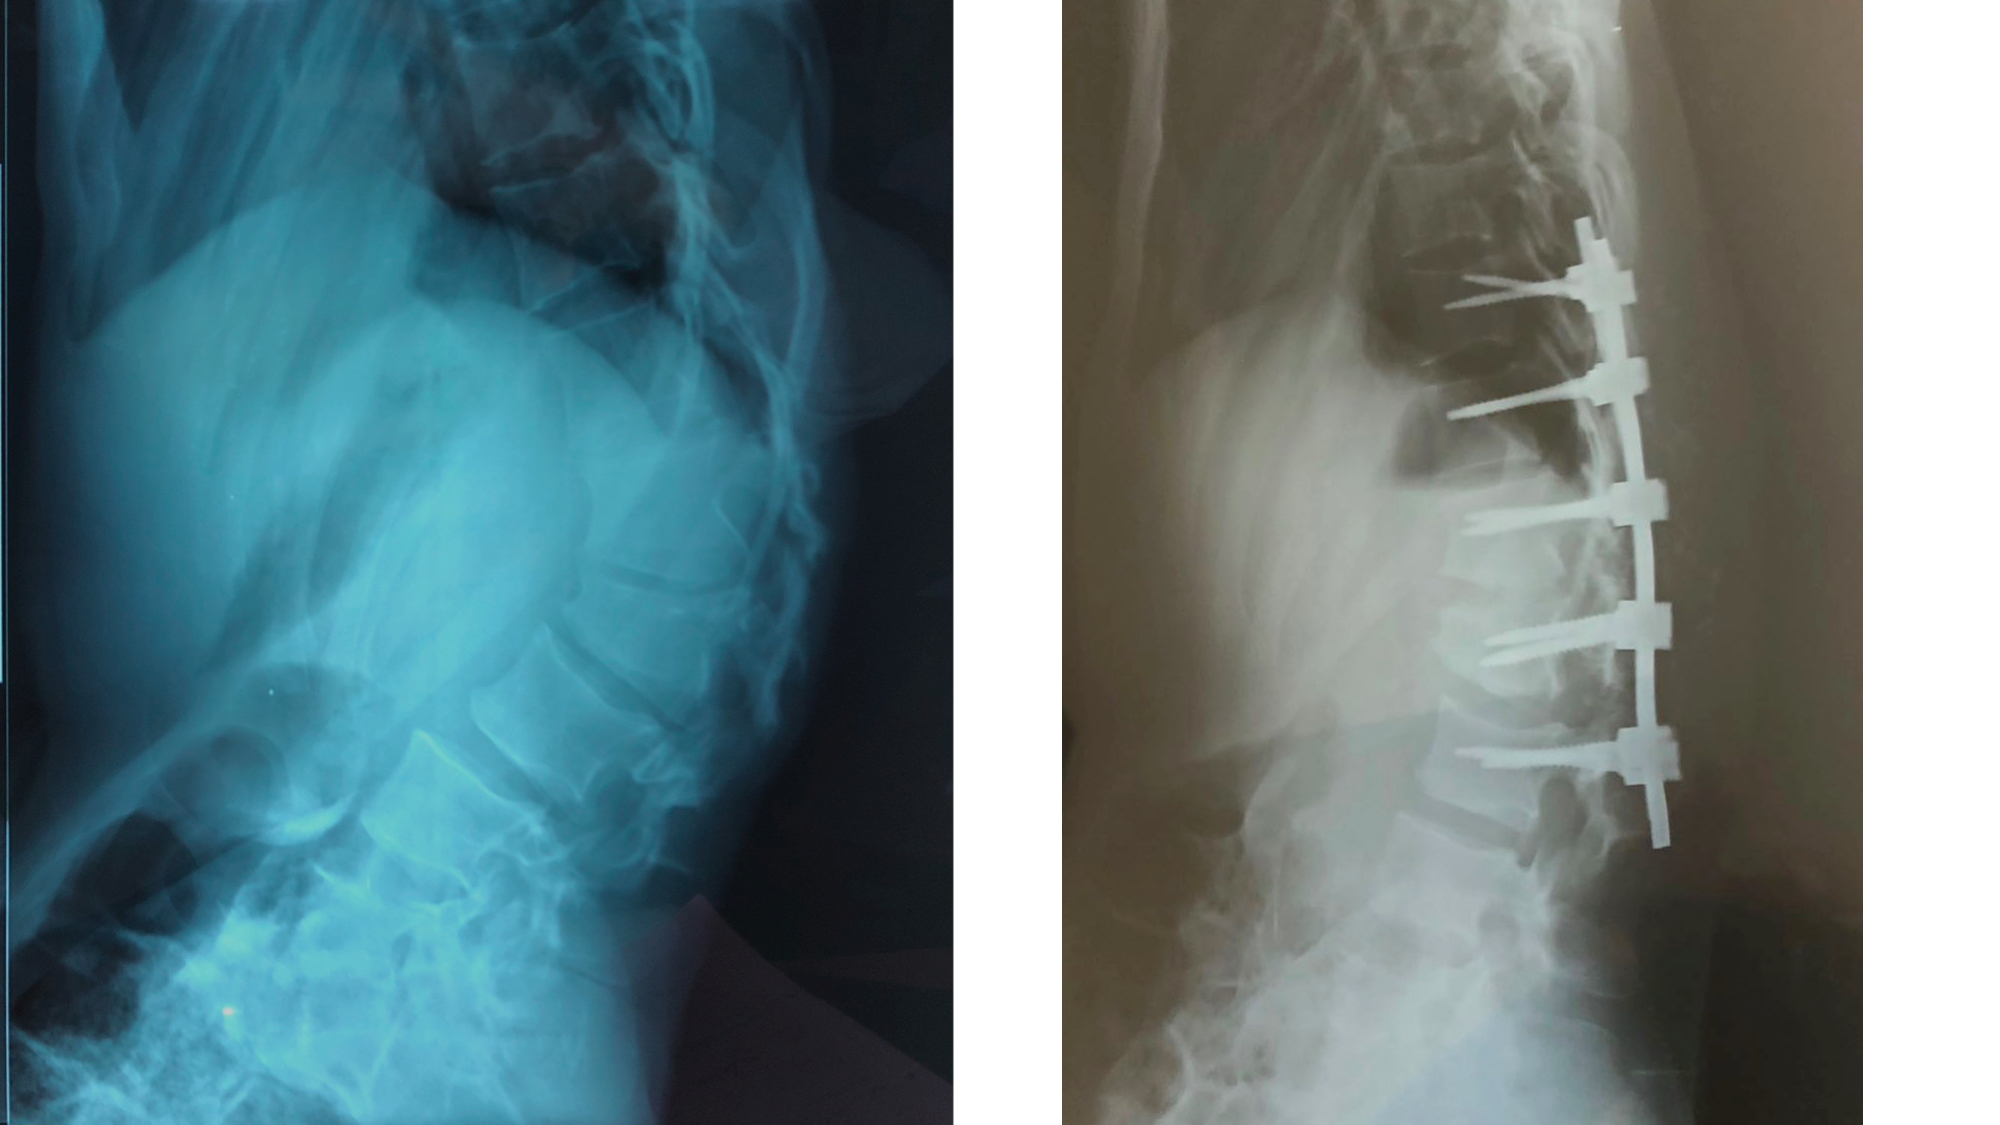

I was also able to meet the first two spine surgery fellows at AaBET. They are both neurosurgeons. The plan after next year is to alternate orthopedic with neurosurgery spine fellows. In addition to their teaching at AaBET, they are mentored by Dr Fasil Mesfin of Univeristy of Missouri, with whom they have weekly cases conferences. They were excited to show me two massive spine tumors they just operated on, one a giant, dumbbell shaped neurofibroma of the lower thoracic spine with bone involvement and preoperative paraparesis; the other a huge aneurysmal bone cyst of posterior lumbar element. Both needed pedicle screw instrumentation and big exposures. I am not a spine surgeon but the operative photos and postop xrays were very impressive.